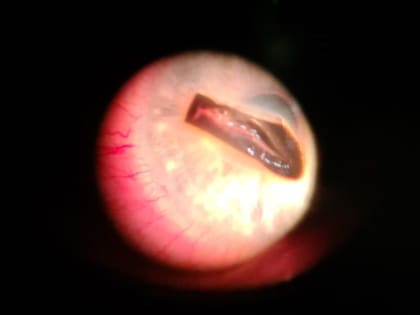

Томские офтальмологи извлекли из глаза пациента осколок металла длиной в 6 мм

Специалисты Томской областной клинической больницы извлекли из глаза пациента металлический осколок, его размер напоминал небольшой орех, сообщили в департаменте здравоохранения.

Томские врачи извлекли из глаза пациента металлический осколок размером с небольшой орех

Томские врачи извлекли из глаза пациента металлический осколок размером с небольшой орех.

Томские врачи удалили из глаза осколок размером с орех

Врачи Томской областной клинической больницы помогли пациенту,